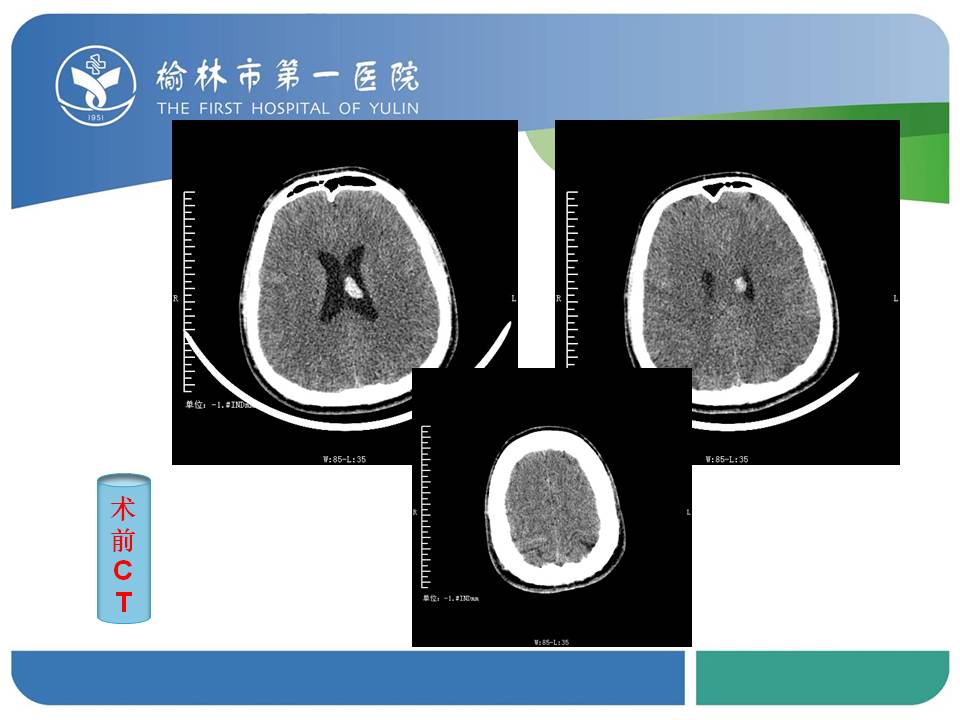

榆林一院神外一病区脑血管畸形切除+微小动脉瘤切除术1例